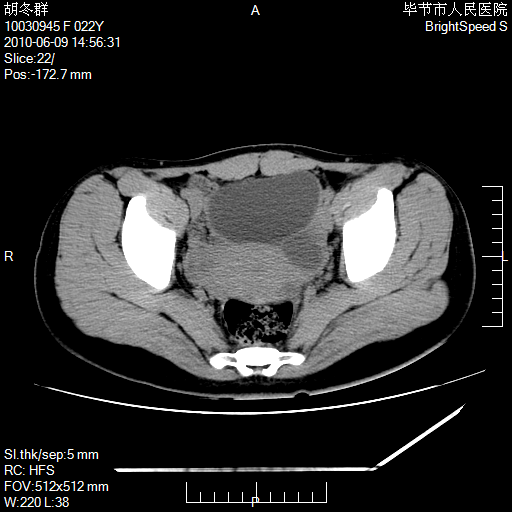

患者23岁,发现腹部包块3月。

盆腔内囊性占位性病变;考虑左侧卵巢囊腺瘤。

支持左侧附件区囊性占位,多考虑为囊腺瘤。

支持考虑左侧卵巢囊腺瘤;宫腔积液。